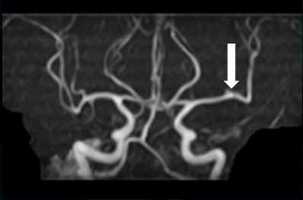

いつもの仕事は何とかこなしていました。最近、ストレスを感じていたこともあって、自分自身では「精神的な問題」と考えていたようです。違和感を心配した友人の勧めで、当院を受診。MRIで、左の中大脳動脈の1本が閉塞(へいそく)した脳梗塞=画像=が描出されました。心臓にできた血栓が原因の脳梗塞と診断しました。再発防止のため、ハートセンターに緊急紹介しました。